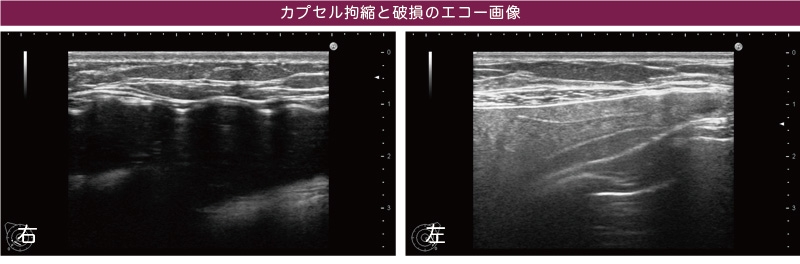

右のバストの黒い部分が波打っているのは、軽度のカプセル拘縮で豊胸シリコンバッグが圧迫され、変形していることが原因。左はその部分が、白濁しているのがわかります。これは豊胸シリコンバッグが破損し、バッグを包み込む被膜(カプセル)の内にシリコンが漏れ出しているためです。

シリコンバッグ豊胸後の軽度のカプセル拘縮は気づかないことも多い

カプセル拘縮は、異物を入れたことによる人体の拒否反応です。豊胸リコンバッグを胸に入れるとすぐに自覚症状が出る人もいますが、緩やかに症状が進み、圧迫された豊胸シリコンバッグがいつの間にか破損することもあるのです。このゲストの方は、まさに時間の経過とともに拘縮がゆっくりと進行していくケースでした。